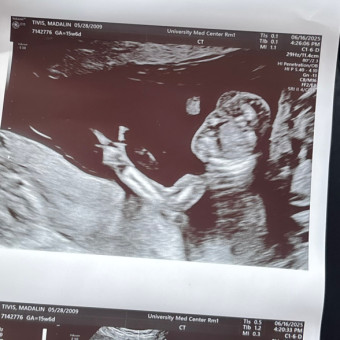

Madi's Baby Registry

Madi Tivis & Xzavier Montano

Portales, NM

December 2, 2025

hii , this is my registry anything you purchase will be highly appreciated i love all you guys so much and thank you !!